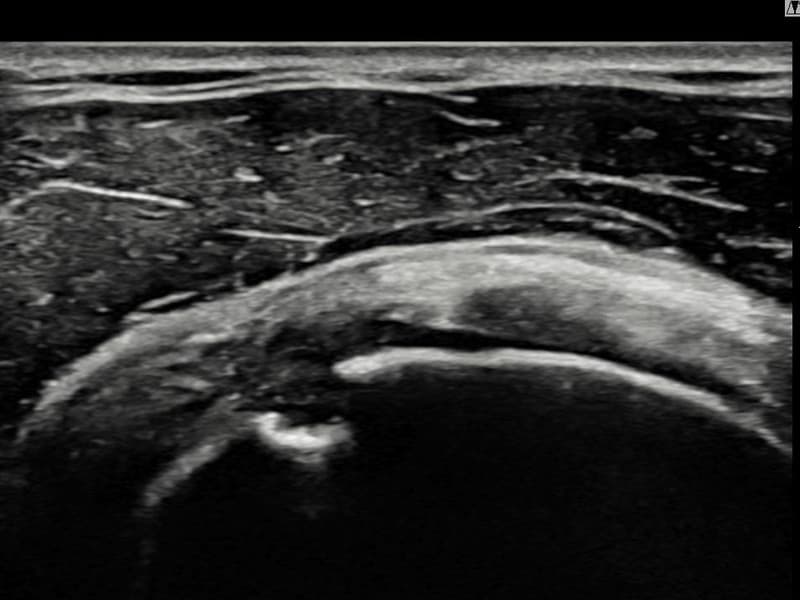

术前

术前超声确认右侧 冈上肌腱 滑囊面侧部分撕裂,右侧冈上肌腱回声不连续伴肌腱缺损(13mm × 6mm (肌腱厚度约62%缺损))。术后超声显示撕裂部位充满再生组织,肌腱连续性恢复,回声模式正常化。

该患者持续肩痛。详细超声检查确认右侧 冈上肌腱 滑囊面侧部分撕裂(缺损:13mm × 6mm (肌腱厚度约62%缺损))。在超声引导下实施非手术缩小缝合术。术后佩戴支具约4-6周,随后进行分阶段康复锻炼。随访超声确认肌腱连续性恢复、结构稳定,患者顺利回归日常生活。